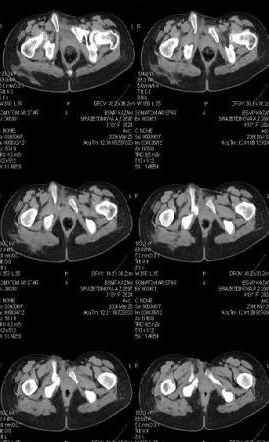

Re: Неправильно сросшийся перелом костей таза

Предоставляю срезы. Если пациентку функционально ничего не беспокоит, стоит ли навязывать ей лечение.